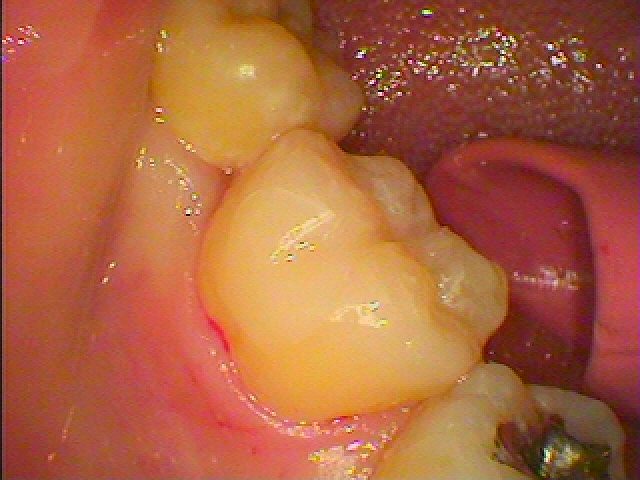

本来の歯のようにきれいに仕上がりました